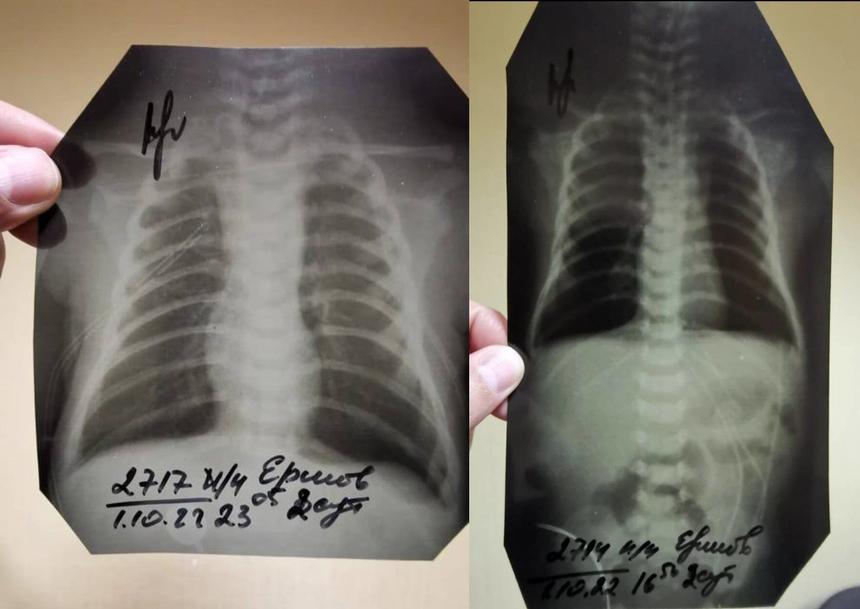

Странности в уликах тоже есть — например, если в прошлом году следователи говорили, что рентгеновские снимки были утеряны больницей, то после жалоб их вдруг нашли, как утверждает отец. Только есть одна деталь — место, в котором обычно аппарат печатает ФИО пациента, врача, проводившего рентген, дату и время процедуры, было вырезано на всех снимках. («Страсти» ознакомились с результатами рентгена).

«Все эти данные обрезаны. Видно, что обрезали это ножницами или чем-то ещё, криво, косо. И просто обычным маркером подписано: Ершов В. Д. Мой сын. А вместо ФИО врача, который проводил процедуру, просто стоит подпись. Интересно, что каждый снимок делался в разные дни и в разное время, а подписи стоят на всех 21 снимках одного и того же врача. Он что, один работает без выходных?», — добавил он.

Обрезанные флюорографические снимки ребенка

© Предоставлено героем публикации

Сам Ершов считает, что снимки, которые внезапно нашлись, на самом деле не принадлежат его ребенку.

Рассказывая об обрезанных снимках, Кириленков допустил, что такое возможно при использовании старого оборудования.

«Да, такое допускается, когда рентген делают на старом оборудовании — по старинке пишут ручкой либо маркером», — добавил он.

Однако отец скончавшегося мальчика заверил, что аппарат для проведения рентгена новый и соответствует всем нормам, а значит и обрезанных частей на снимках быть не должно.